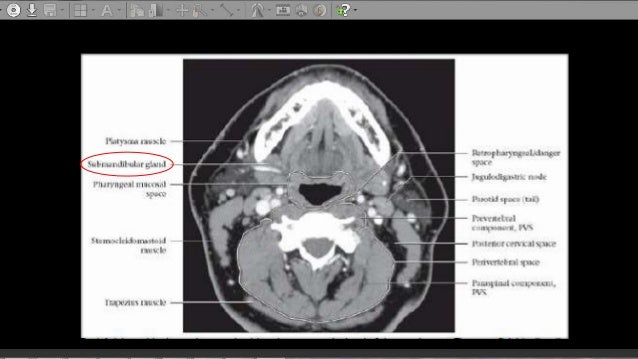

CT Anatomy Of Neck Spaces RV

CT anatomy of Neck Spaces RV www.slideshare.net

digastric submandibular mylohyoid gland sublingual